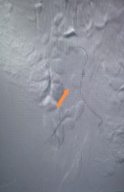

手术在全麻下进行。团队通过双侧股动脉入路,同时建立左桡动脉通路以确保精准输送。首先超选肠系膜下动脉并完成弹簧圈栓塞;随后依次释放腹主动脉主体支架、右侧髂支及IBD主体支架;最后经桡动脉路径将覆膜支架精准送入左髂内动脉并释放。术中球囊后扩张各连接处,最终造影显示:腹主动脉、双侧髂总、髂外及髂内动脉均通畅,无内漏,瘤腔完全隔绝——手术圆满成功。

栓塞肠系膜下动脉

释放左髂内动脉分支